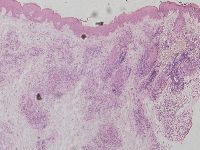

De infiltraten kunnen voornamelijk uit B-lymfocyten of T-lymfocyten of een mix

van beide opgebouwd zijn en zijn perivasculair en perifolliculair gelegen. Er

is doorgaans enige grensvlakdermatitis met minimale atrofie te zien. Klinisch

Histopathologisch onderzoek:

Vacuolaire grensvlakcomponent. In de dermis bevinden zich rondom de vaten en

adnexstructuren dichte lymfocytaire infiltraten opgebouwd uit CD3 positieve

T-lymfocyten en CD20 positieve B-lymfocyten met focaal de neiging tot kiemcentrumvorming.

Immunofluorescentie-onderzoek toont geringe discontinue granulaire deposities

van IgM en C3 langs de basale membraan.